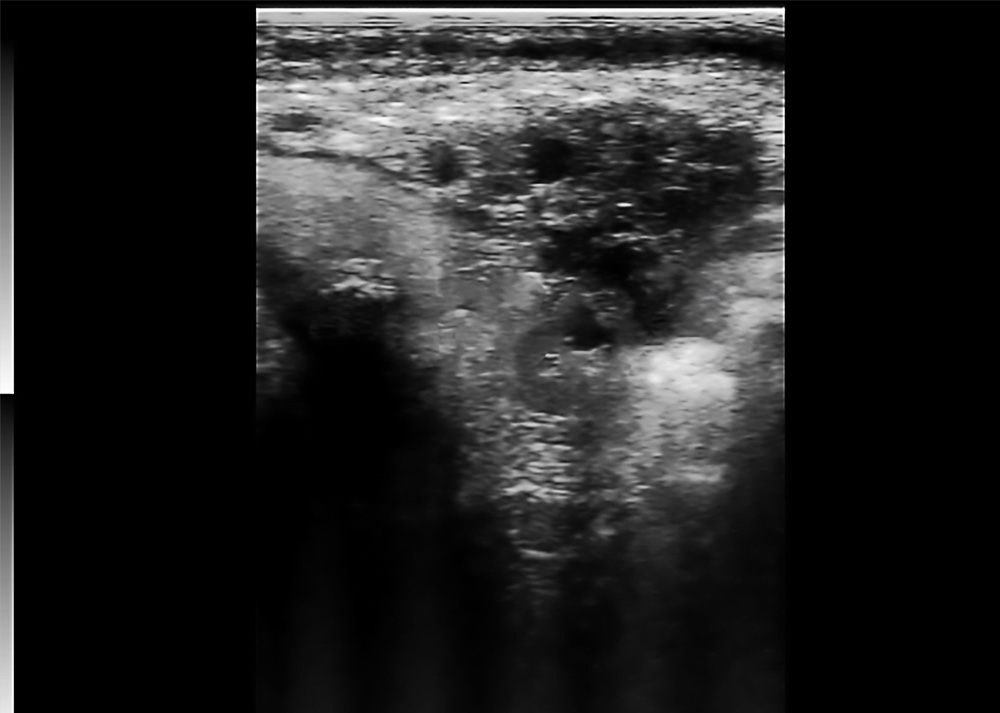

Bovine Pregnancy Ultrasound

● Depicts early gestational structures with clear contours.

● Stable contrast highlights fluid-filled zones.

● Outlines embryo–uterus spatial relation.

● Supports pregnancy stage evaluation.